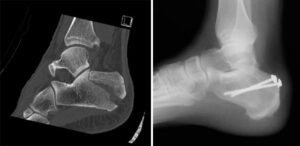

(Left) In some injuries, the talus is forced downward and acts like a wedge to fracture the calcaneus. (Right) This computerized reconstruction of a calcaneus fracture shows the amount of damage that can occur.

(Left) A displaced fracture of the calcaneus. (Right) The fracture has been reduced and the bones held in place with screws.